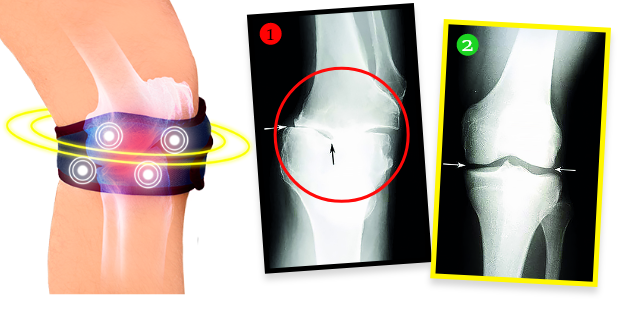

Paní Helena si po kúře nechala udělat rentgen, ukázalo se, že degenerativní změny v koleni zcela zmizeli! Lékař byl ohromen – nevěděl, co říct. Faktem je, že díky biomagnetickému pásku se stav kolena paní Heleny nejen přestal zhoršovat, ale chrupavka a jemné struktury v oblasti kloubu se zregenerovaly a koleno je opět plně funkční, stejně jako před lety. Pásek totiž vyzařuje přírodní a bezpečné biomagnetické pole, které proniká do nejhlubších tkání kloubu, vyživuje a regeneruje chrupavku, vrací jí pružnost a elasticitu, zároveň stimuluje produkci kloubního mazu, který tlumí a chrání před bolestivým třením při pohybu. Jde o plně neinvazivní a bezpečnou terapii.